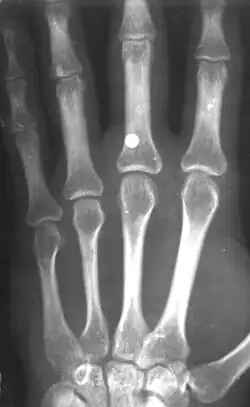

BB gun injury showing a 4.5 mm steel BB that penetrated the middle finger on the left hand

A BB with a velocity of only 45 m/s (150 ft/s) has skin-piercing capability, and a velocity reaching 60 m/s (200 ft/s) can fracture bone.[7] This is potentially lethal, and this potential increases with velocity, but also rapidly decreases with distance. The effective penetrating range of a BB gun with a muzzle velocity of 120 to 180 m/s (390 to 590 ft/s) is approximately 18 m (60 ft). A person wearing jeans at this distance would not sustain serious injury. However, even at this distance a BB still might penetrate bare skin, and even if not, could leave a severe and painful bruise. The maximum range of a BB gun in the 120 to 180 m/s (390 to 590 ft/s) range is 100–200 metres approximately,[8] provided the muzzle is elevated to the optimum angle.